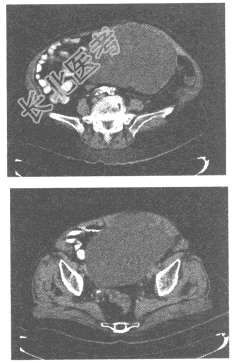

- 单项选择题女,42岁, 盆腔占位,根据所提供的CT图像, 最可能的诊断是

A、子宫肌瘤

B、卵巢癌

C、卵巢畸胎瘤

D、卵巢囊肿

E、卵巢浆液性囊腺瘤